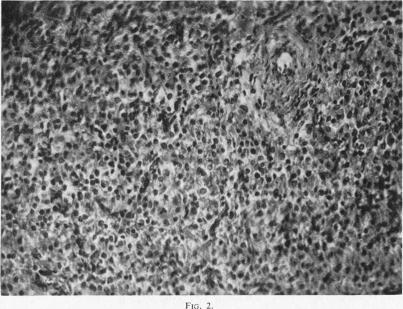

MALIGNANT CAROTID BODY TUMOUR IN THE NECK OF A NEWBORN INFANT.

Arch Dis Child. 1964 Apr;39(204):194-6. doi: 10.1136/adc.39.204.194.